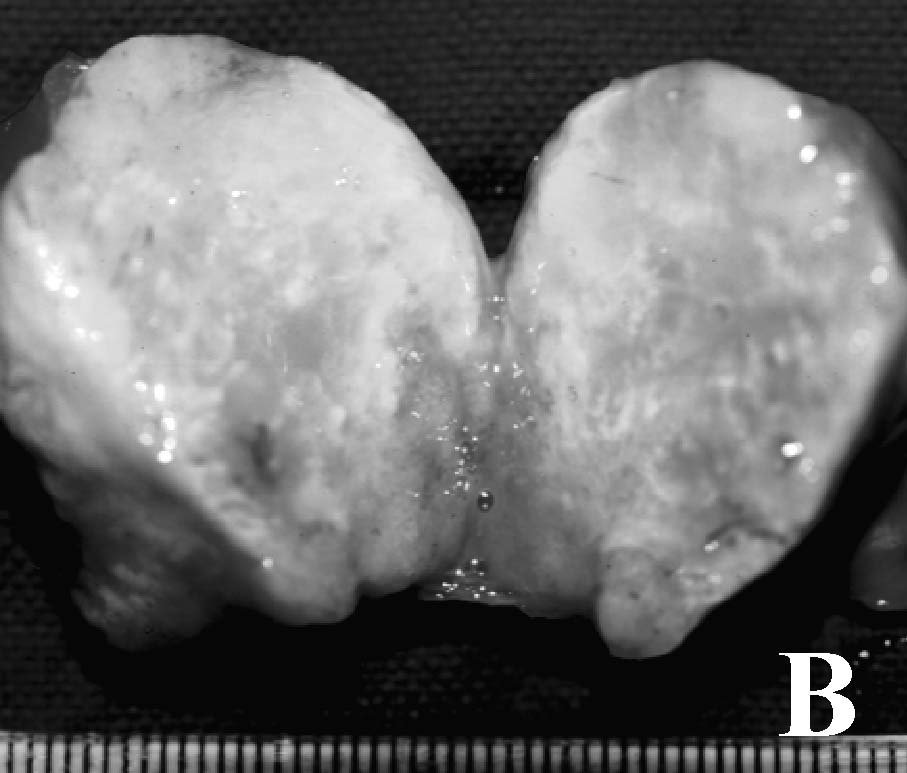

Figure 1. A subcutaneously

implanted hamster. A. Appearance before tumor resection. B.

Panoramic view after resection. C. Resected specimen without the

covering skin. D. Histopathologic view

showing a moderately differentiated adenocarcinoma (H&E, 200x). |

Success

rate of Implantation, Appearance of Resected Tumors and Survival Time

All 35 animals developed tumors at

the site of implantation, palpable after one week. At the time of resection,

the diameter of the tumor ranged between 18 and 22 mm. Five hamsters in the STI

group, but none in the SCI group, showed adhesion to deep tissue. The skin

covering the tumor was adhered in all animals of both groups. All tumors showed

a well-circumscribed surrounding capsule. Some necrosis was found in the center

of all tumors in the SCI group, and in the center and periphery of all tumors

in the STI group. All resected specimens were confirmed histologically as

moderately differentiated adenocarcinoma. However, tumors of the STI group

consisted of more connective tissue, as shown in Figure 1. Thus, the success

rate of implantation was 100%. The mean survival time in the SCI group was 151±